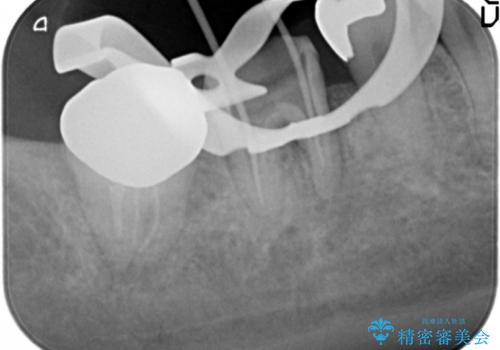

歯ぐきの腫れが治らない 石灰化した狭小根管治療

- 他院で根管治療を受け銀歯をかぶせるところまで行ったが、直後より腫れ・痛みが引かず当院へ相談、来院されました。

X線写真検査より根管充填の行われていない根管、視診より歯肉からの排膿路を認め、急性根尖性歯周炎の治療として根管再治療を計画します。

治療途中、マイクロスコープでも根管が追えないほど狭く細くなった根管へと変性しており根管の拡大形成が難しい状況でした。

CTを撮影し少しづつ丁寧に根管を探索することで無事根管再治療を行い、症状がなくなりました。